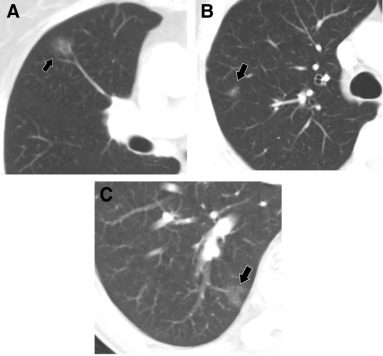

部分实性GGN可能是由于感染引起的,并且可能在短期随访后消退,因此建议3~6个月进行一次随访以确认其是否持续存在【1】。有研究显示,≥6 mm的纯GGN可以安全地进行随访,其生长缓慢,通常需要3~4年才能长大或新增实性成分。

经大规模临床统计证实:并不是所有的肺部磨玻璃结节都会变化,事实上,对于小的磨玻璃结节,比如小于5mm的结节,发展的风险是很低的,约在10%。而且磨玻璃结节的发展也非常缓慢,是以年计算的,所以不要频繁的做CT,也不要紧张会在随访中突然变大扩散。

6mm-8mm的磨玻璃结节恶性率可以达到6%~28%;因此,按要求进行随访还是非常有必要的。

对于炎症造成的磨玻璃结节在随访期间,结节可以缩小或淡化,也可完全消失,如果随访期间结节没有变化或有微小的变化,还是建议继续给予随访,根据随访结果选择进一步诊疗的方式。